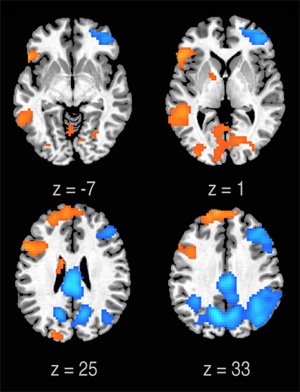

fMRI is one of the main tools of neuroscience. It images bloodflow in the brain and illuminates which regions of the brain are working hard. 12 professional rappers boasting a minimum of 5 years experience were enlisted for the experiment. Each participant was given 8 bars worth of lyrics to memorise a week before the brain scan. This provided the “conventional” control experiment against which improvisation could be gauged. The improvisation experiment tasked the rappers with freestyling over the same 8 bar segment of music.

The findings of the study were interesting: when the rappers were improvising their brains entered a state of 'flow'. Several regions of the brain involved in sensory experience were activated and connected, while self-control was inhibited. This suggests that genuine immersion in the moment is commensurate with, if not essential to, spitting lyrical genius.